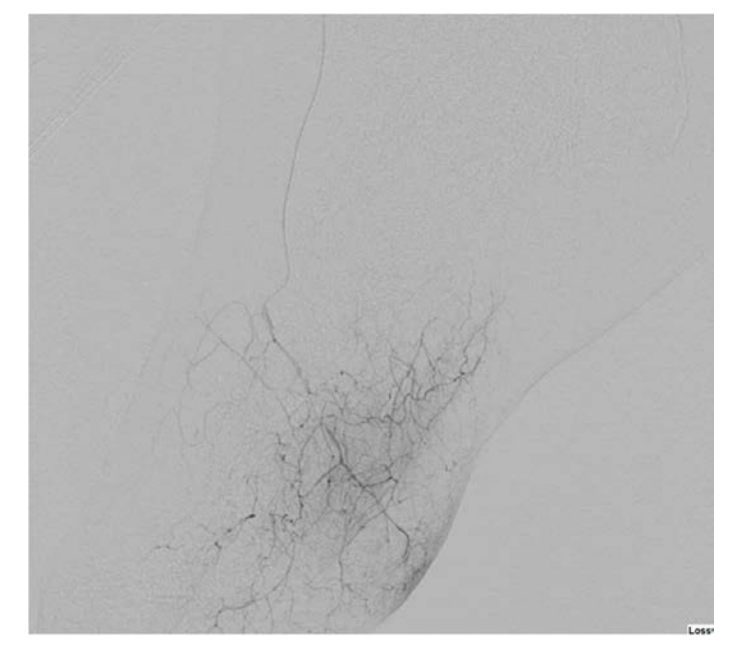

On examination, his right dorsal pedis and posterior tibialis pulses were absent. His right heel had a mature eschar on the posterior aspect with no erythema, drainage, or odor noted in addition to wounds involving his second to fifth digits. Bedside Doppler showed a diminished signal at the dorsal pedis and absent signal at the right posterior tibial. X-ray of the foot demonstrated no evidence of osteomyelitis. His vascular arterial Duplex ultrasound showed an occluded right posterior tibial DVA. The distal anterior tibial artery was severely diseased with a distal occlusion and a monophasic waveform (Figure 1A and 1B). The distal peroneal and posterior tibial arteries were occluded. The plantar veins were studied with ultrasound for possible targets for hybrid DVA using a great saphenous vein to medial marginal vein bypass; however, this was not favored after discussing with vascular surgery. He was evaluated for right below knee amputation which he refused. He was then transferred to our facility to consider other treatment options for revascularization as a last resort. He had a peripheral angiogram that showed a patent distal aorta, iliac arteries, and femoropopliteal segments. The right anterior tibial artery was diffusely diseased with a 90% critical stenosis in its distal segment (Figure 2). The right distal peroneal, posterior tibial arteries and the right posterior DVA were occluded. After careful analysis of the angiogram, we proceeded with an intervention to the anterior tibial artery to establish direct foot perfusion. The left common femoral artery was accessed under ultrasound guidance using a micropuncture needle. A 4F IMA diagnostic catheter and a 0.035 angled Glidewire were used to access the contralateral right common iliac artery. The right SFA and profunda femoral arteries were heavily calcified without severe obstructive disease. The wire was advanced into the right popliteal artery and a 5F by 90 cm Cook Flexor Shuttle was advanced to the origin of the right anterior tibial artery for good support. An Asahi Sion Black 0.014 x 300 cm guidewire was advanced and used to cross the distal anterior tibial stenosis into the dorsal pedis artery. The distal wire was advanced into the first dorsal metatarsal branch after several attempts to wire across the pedal loop. A Corsair Asahi 150 cm microcatheter was then advanced into the dorsal pedis artery and selective foot angiogram was performed. A magnified view of the right foot showed a chronic total occlusion of the dorsal pedis (Figure 3). Laser atherectomy was performed with Philips Turbo Elite 0.9 mm catheter from the origin of the anterior tibial artery to the beginning of the dorsal pedis artery at 80/80 fluency/rate (Figure 4). This was followed by balloon angioplasty with coronary balloons since other balloons will not cross at rated pressure with multiple prolonged 5-minute inflations each of the entire vessel. A Coyote 2.5 x 220 mm balloon was used to further postdilate the anterior tibial artery obtaining excellent angiographic result with improvement of the blood flow into the dorsal pedis as well as the collaterals to the posterior tibial and its plantar branches. The patient’s ischemic rest pain resolved and he was followed linearly along wound care with significant improvement few weeks later.